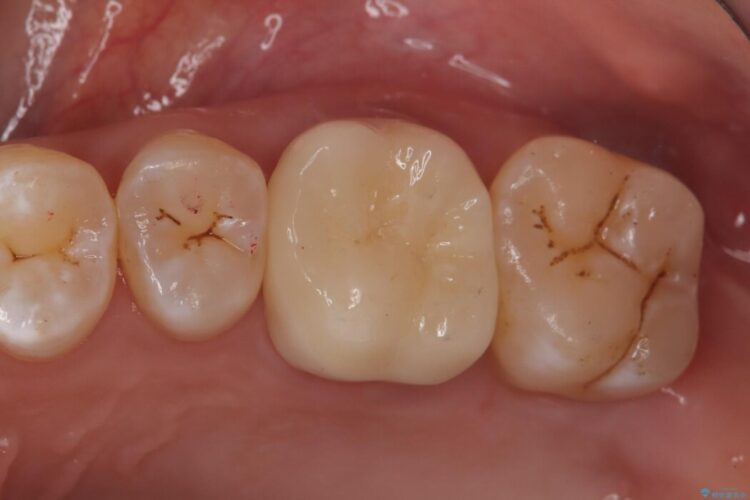

食べ物を噛んだ時に歯がしみる、ズキズキ痛む、長引く痛み。不可逆性歯髄炎の治療

食事の際に歯がしみてしまう、また最近になって何もしていないのにズキズキ痛んだり長引いている痛みがある、とのことで来院されました。